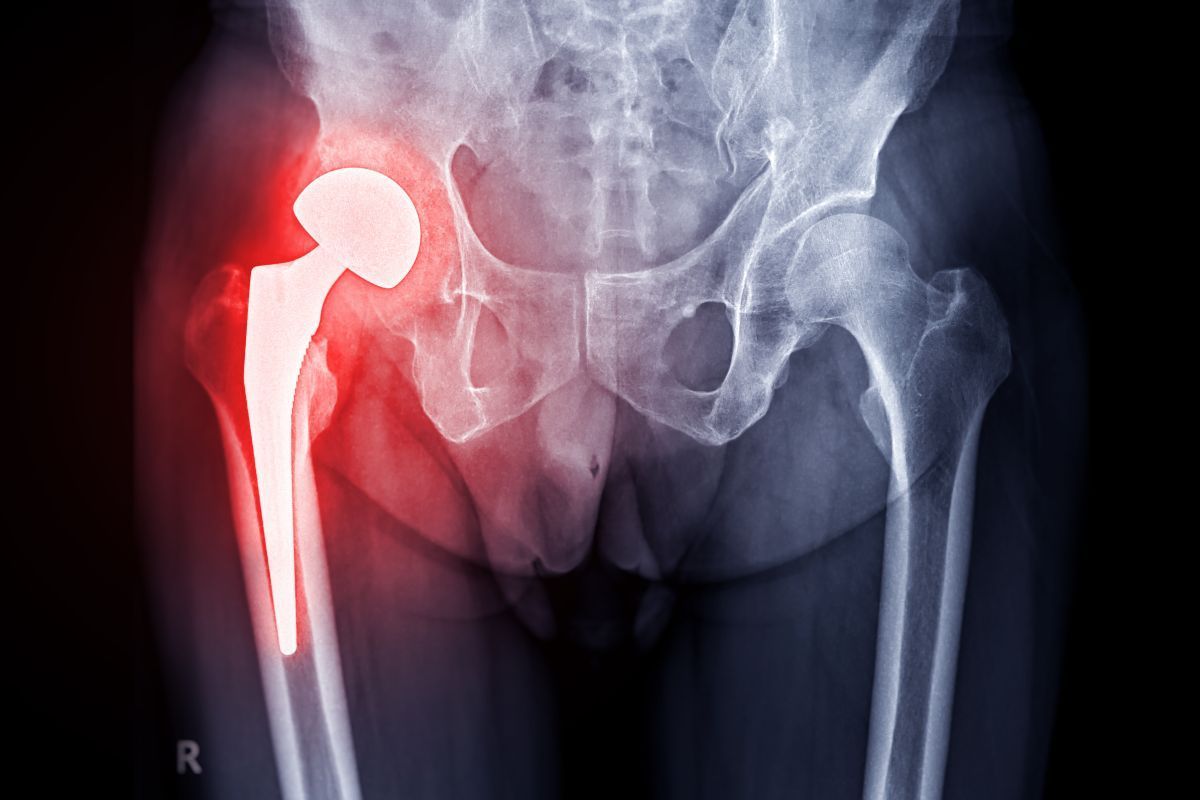

A cirurgia de revisão da prótese de quadril é um procedimento ortopédico realizado para substituir parcial ou totalmente uma prótese previamente implantada que deixou de funcionar de maneira adequada.

Indicamos esse procedimento quando ocorre falha do implante, seja por soltura dos componentes, desgaste dos materiais, infecção, fratura ao redor da prótese, desalinhamento ou dor persistente que compromete a função e a qualidade de vida do paciente.

A radiografia, por exemplo, nos permite identificar sinais de soltura, desgaste dos componentes, desalinhamento, fraturas ao redor da prótese ou alterações ósseas.